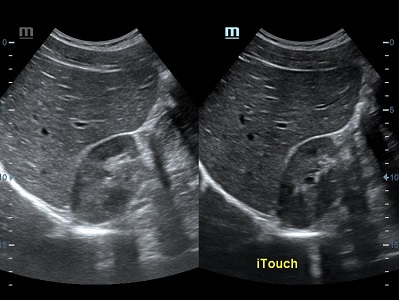

Обзор функции УЗИ: iTouch - автоматическая оптимизация изображения

Оптимизация изображения происходит и за счет постобработки. Наиболее часто используемый инструмент - общее усиление (Gain). Усиление делает изображение «ярче», но чем сильнее усиление, тем меньше различия между структурами. Также используются усиление по времени (TGC) и усиление по длине (LGC), которые позволяют изменять отображение на экране послойно, позволяя подсветить гипоэхогенные участки, или, наоборот, снизить визуально эхогенность слишком ярких моментов. Данный вид оптимизации требует много времени, для упрощения работы доктора на приборах Mindray внедрена система автоматической оптимизации - iTouch.